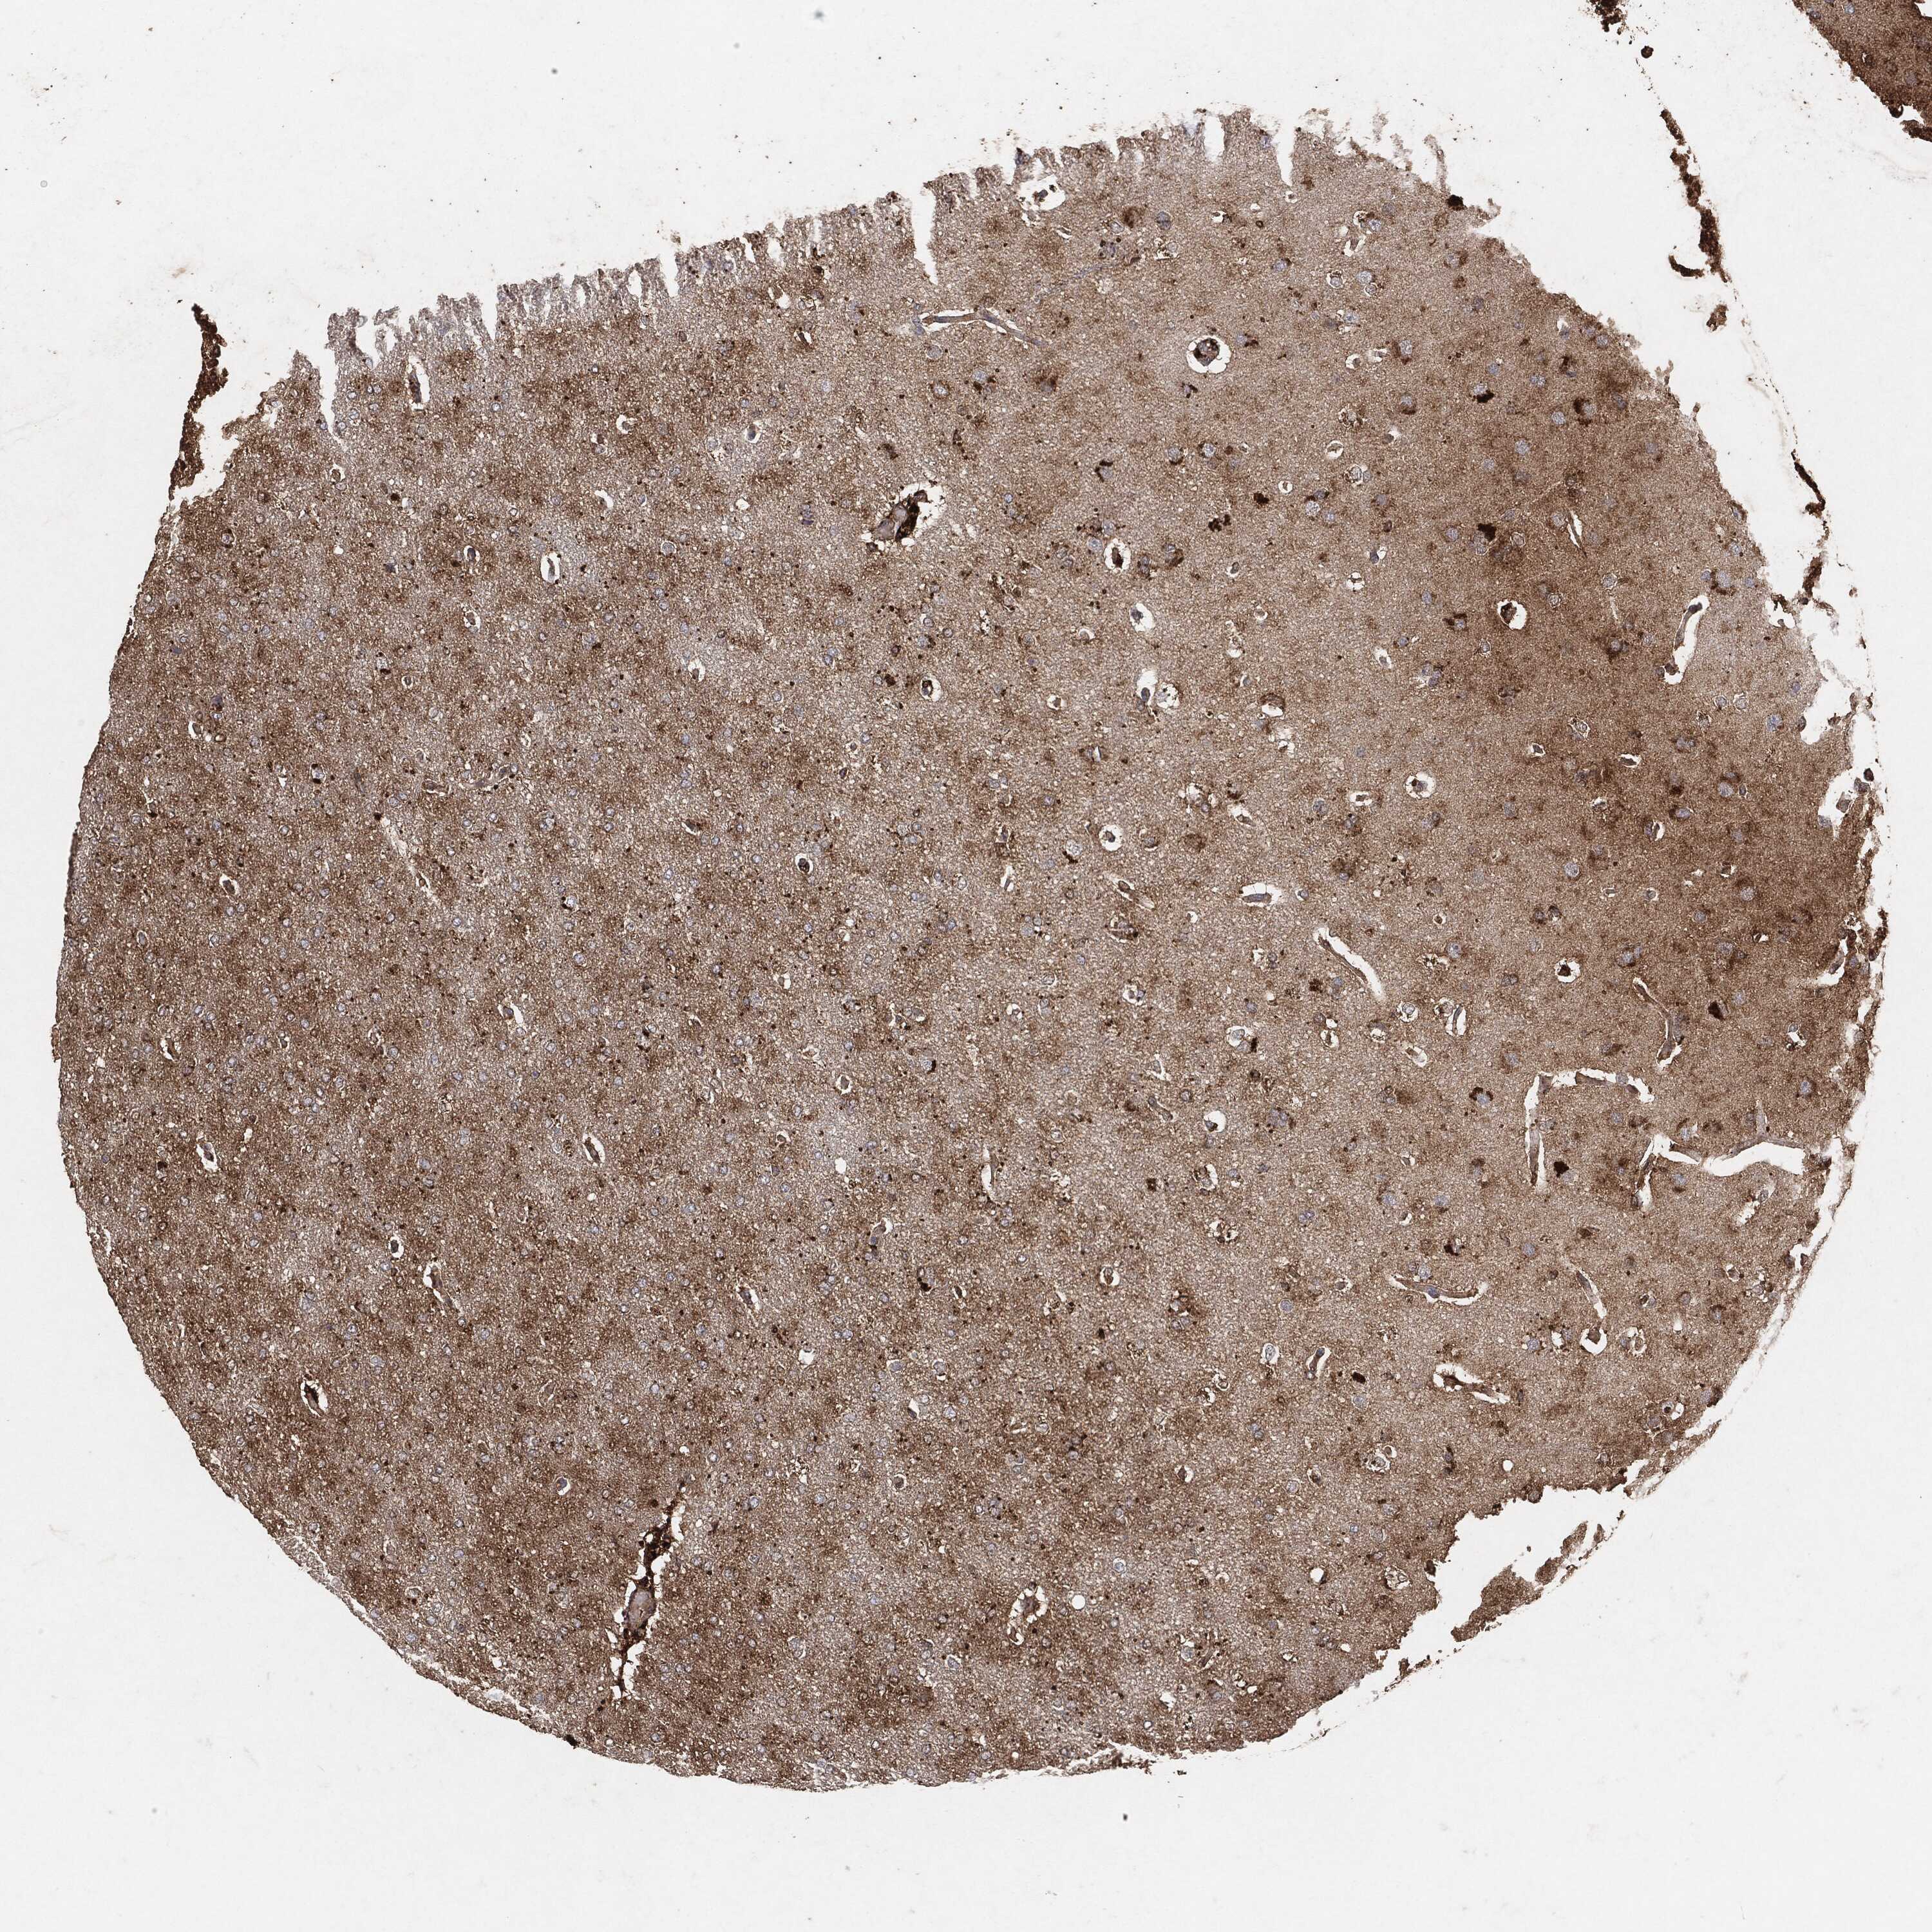

GLIOMA - Protein expressioni

A mouse-over function shows sample information and annotation data. Click on an image to view it in a full screen mode. Samples can be filtered based on level of antibody staining by selecting one or several of the following categories: high, medium, low and not detected. The assay and annotation is described here.

Note that samples used for immunohistochemistry by the Human Protein Atlas do not correspond to samples in the TCGA dataset.

Antibody stainingi

Antibody staining in the annotated cell types in the current human tissue is reported as not detected, low, medium, or high, based on conventional immunohistochemistry profiling in selected tissues. This score is based on the combination of the staining intensity and fraction of stained cells.

Each image is clickable and will lead to virtual microscopy that enables deeper exploration of all samples and also displays staining intensity scores, fraction scores and subcellular localization as well as patient and tissue information for each sample.

Glioma, malignant, High grade

Glioma, malignant, Low grade

Glioma, malignant, NOS